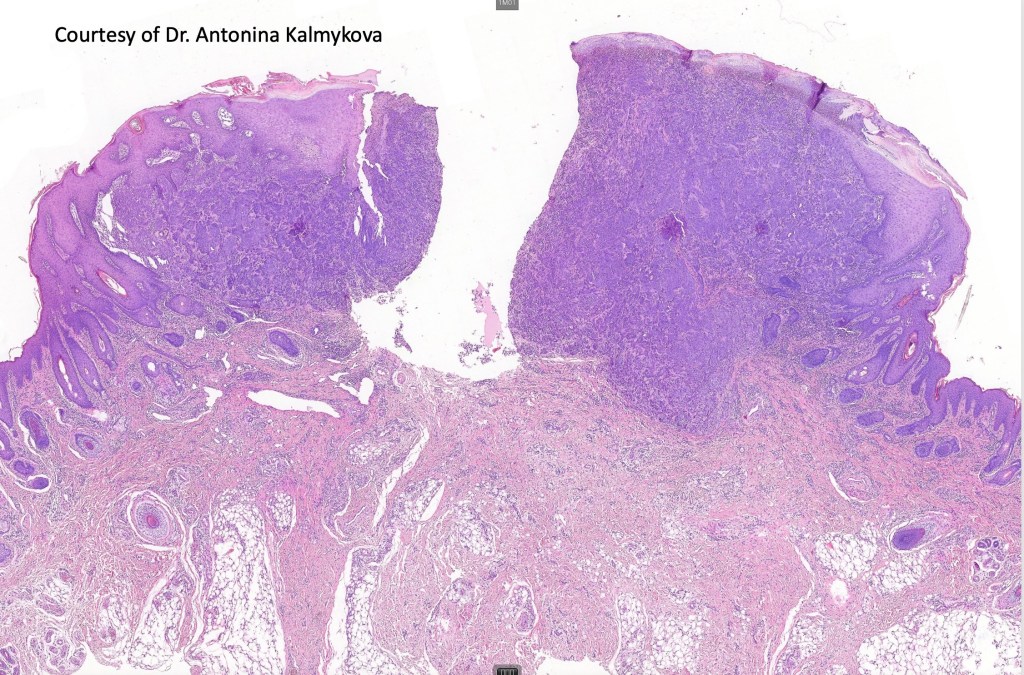

Histological features

•>5-10 mm

•Involve deep dermis or subcutis

•Asymmetrical, poorly circumscribed

•May show effacement/consumption of epidermis or ulceration

•Peripheral Pagetoid spread

•Large nodules which often show impaired maturation

•Loss of gradient with HMB45 and Ki67

•>20% Ki67 expression

•TERT promoter & PTEN mutations

•DNA copy-number variations